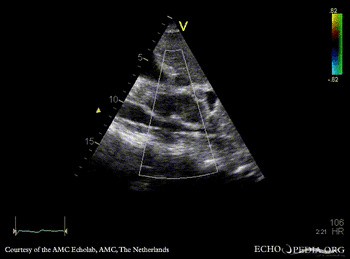

Obstruction of vena cava inferior

Subcostal view: obstruction of vena cava inferior from outside the heart Subcostal view with Color Doppler